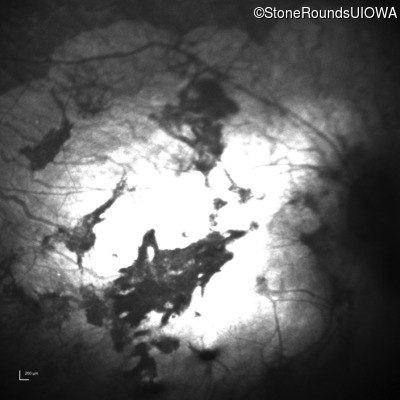

Infrared Fundus Photograph - Right - Light Perception

Exemplar